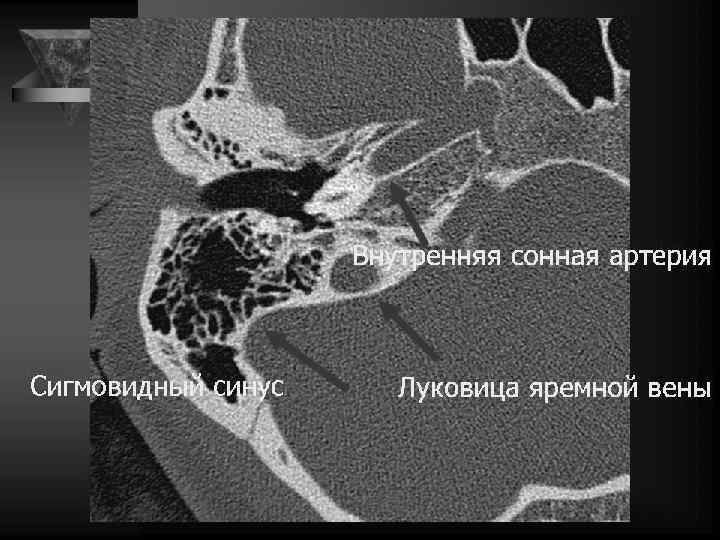

Среднее ухо • Содержимое: потеря воздушности. • Локализация и наличие патол. образований. • Слуховые косточки: вывих, деструкция, анкилоз. • Состояние круглого и овального окна. • Состояние горизонтальной части канала лицевого нерва. • Область расположения коленчатого ганглия. • Барабанная перепонка: утолщена, втянута. • Положение и контуры внутренней сонной артерии, сонного канала. • Положение яремной ямки, состояние луковицы внутренней яремной вены